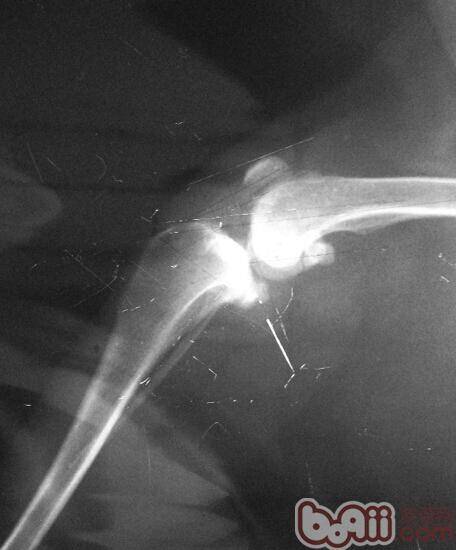

膝关节x光

术前,我们的冼医生为之进行了简单的理学检查。我们重新拍摄了膝关节x光,计算了手术的植入物宽度。准备好之后,我们开始对动物麻醉,上了监护。在消毒好,我们手术开始了十分钟之前,任麻醉师的冼医生示意让我停止手术。我不解,但必须听指挥。要知道,手术中最高权力者非主刀医师,而是麻醉师。